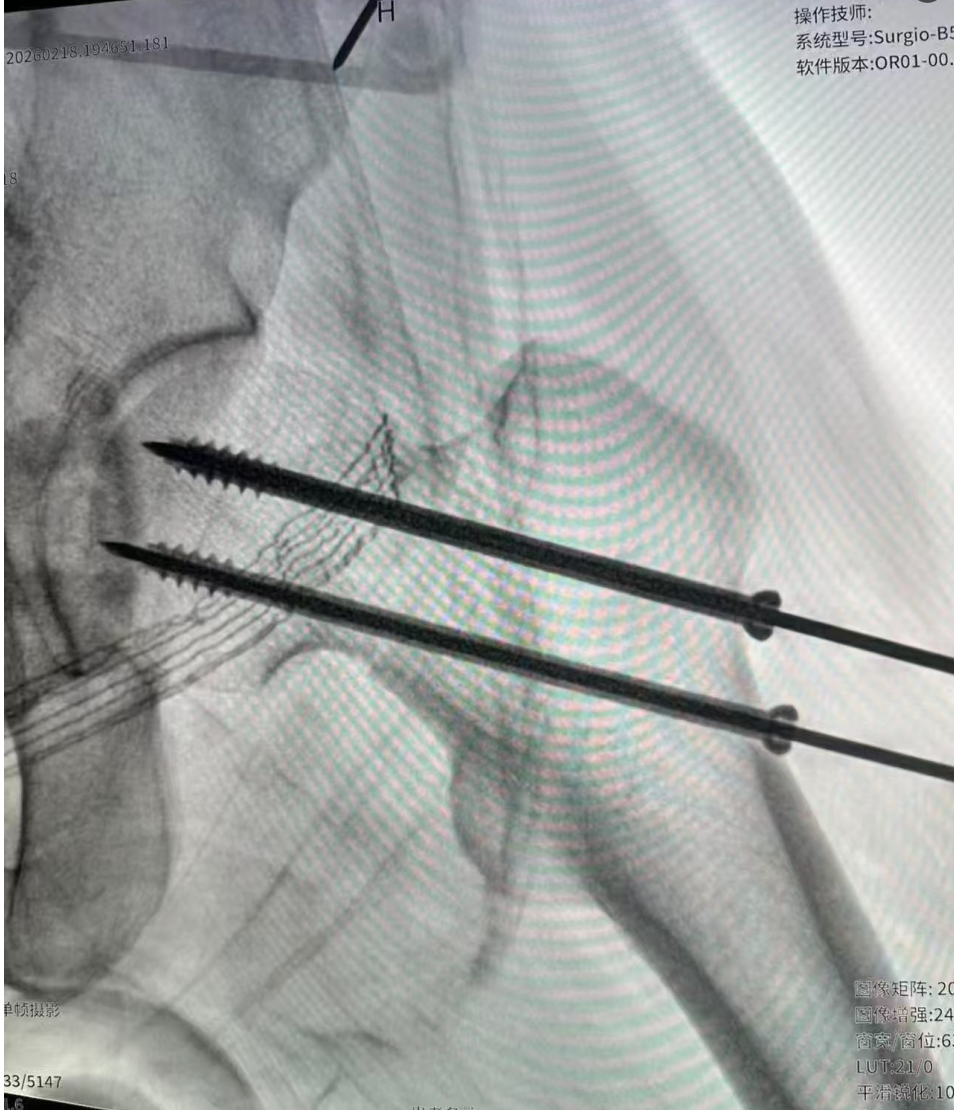

在骨科手术导航机器人的辅助下,团队精准复位骨折端,置入内固定装置,手术过程一气呵成,没有出现任何并发症。